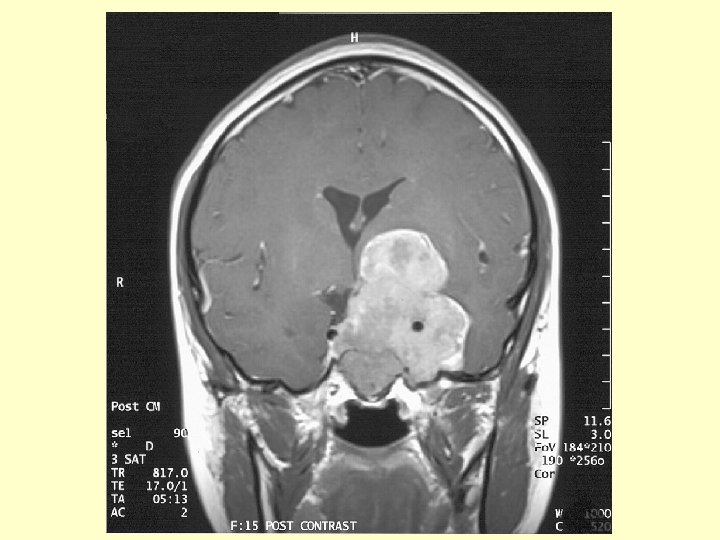

Investigation (3) • CT scan brain: A large hyperdense mass at the left parasellar region. It measured 4. 6 x 4. 4 cm. No calcification or cystic component found. It was extra-axial in location & extended into the pituitary fossa, middle & posterior cranial fossae. The left carotid artery was encased. The optic chiasm was compressed. There was mild hydrocephalus noted due to compression at level of Foramen of Monro.

Investigation (4) • MRI brain: A contrast enhanced solid tumor , measuring 4. 6 x 4. 8 x 6. 3 cm , was occupying whole sella with superior & inferior extension. Superiorly it extended to suprasellar cistern compressing left hypothalamus with the left cerebral peduncle being compressed & elevated. The frontal horn of left lateral ventricle was compressed from below. The left carotid artery was encased by tumor. The optic chiasm could not be identified but was likely to be compressed & encased.

Investigation (5) • MRI brain ( cont’d) Laterally the mass was compressing left temporal lobe & was occupying cavernous sinuses & Meckel’s cave. The mass also occupied right cavernous sinus & encasing right carotid artery. Inferiorly, the mass eroded through sellar floor & occupied sphenoid sinus with floor of sphenoid sinus preserved. Posteriorly the mass extended into left cerebellopontine angle cistern and caused compression of left of pons. Fourth ventricle not distorted.